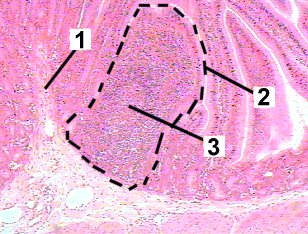

This figure is a high magnification of a Peyer's patch in the ileum.

Fig 41-005 |